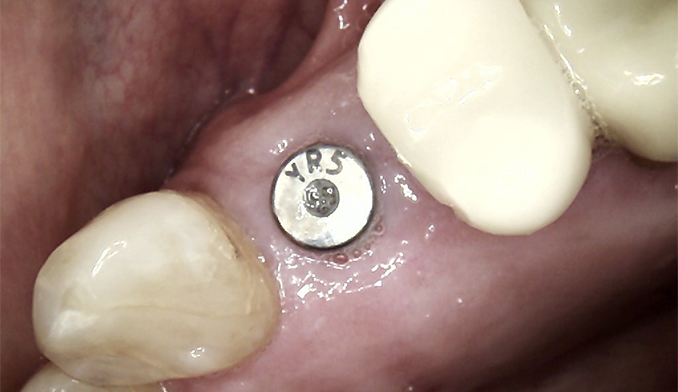

Sinus Lift and Implant Placement for Missing Molar

The patient wished to replace a missing upper left molar. To allow placement of an appropriately sized implant for long-term success, we performed a crestal sinus lift to gently raise the sinus floor. Bone grafting was completed at the same time, and the dental implant was placed in a single procedure to restore the missing tooth.